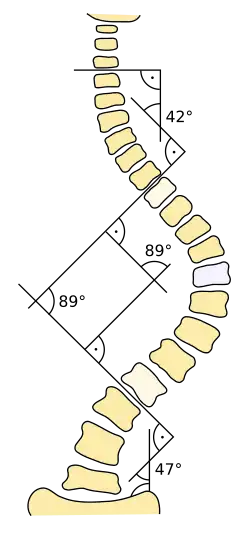

When scoliosis is suspected, weight-bearing, full-spine AP/coronal (front-back view) and lateral/sagittal (side view) X-rays are usually taken to assess the scoliosis curves and the kyphosis and lordosis, as these can also be affected in individuals with scoliosis. Full-length standing spine X-rays are the standard method for evaluating the severity and progression of scoliosis, and whether it is congenital or idiopathic in nature. In growing individuals, serial radiographs are obtained at 3- to 12-month intervals to follow curve progression, and, in some instances, MRI investigation is warranted to look at the spinal cord.[80] An average scoliosis patient has been in contact with around 50–300 mGy of radiation due to these radiographs during this period.[81]

The standard method for assessing the curvature quantitatively is measuring the Cobb angle, which is the angle between two lines, drawn perpendicular to the upper endplate of the uppermost vertebra involved and the lower endplate of the lowest vertebra involved. For people with two curves, Cobb angles are followed for both curves. In some people, lateral-bending X-rays are obtained to assess the flexibility of the curves or the primary and compensatory curves.

Scoliosis is defined as a three-dimensional deviation in the axis of a person's spine.[46][7] Most instances, including the Scoliosis Research Society, define scoliosis as a Cobb angle of more than 10° to the right or left as the examiner faces the person, i.e. in the coronal plane.[86]

Treatment for idiopathic scoliosis also depends upon the severity of the curvature, the spine's potential for further growth, and the risk that the curvature will progress. Mild scoliosis (less than 30° deviation) and moderate scoliosis (30–45°) can typically be treated conservatively with bracing in conjunction with scoliosis-specific exercises.[4] Severe curvatures that rapidly progress may require surgery with spinal rod placement and spinal fusion. In all cases, early intervention offers the best results.

Indications for bracing: People who are still growing and who present with Cobb angles less than 20° should be closely monitored. People who are still growing and present with Cobb angles of 20 to 29° should be braced according to the risk of progression by considering age, Cobb angle increase over a six-month period, Risser sign, and clinical presentation. People who are still growing and present with Cobb angles greater than 30° should be braced. However, these are guidelines, and not every person will fit into this table.

For example, a person who is still growing with a 17° Cobb angle and significant thoracic rotation or flatback could be considered for nighttime bracing. On the opposite end of the growth spectrum, a 29° Cobb angle and a Risser sign three or four might not need to be braced because the potential for progression is reduced.[101] The Scoliosis Research Society's recommendations for bracing include curves progressing to larger than 25°, curves presenting between 30 and 45°, Risser sign 0, 1, or 2 (an X-ray measurement of a pelvic growth area), and less than six months from the onset of menses in girls.[102]

Surgery is usually recommended by orthopedists for curves with a high likelihood of progression (i.e., greater than 45–50° of magnitude), curves that would be cosmetically unacceptable as an adult, curves in people with spina bifida and cerebral palsy that interfere with sitting and care, and curves that affect physiological functions such as breathing.[104][105]

Surgery is indicated by the Society on Scoliosis Orthopaedic and Rehabilitation Treatment (SOSORT) at 45–50°[4] and by the Scoliosis Research Society (SRS) at a Cobb angle of 45°.[106] SOSORT uses the 45–50° threshold as a result of the well-documented, plus or minus 5° measurement error that can occur while measuring Cobb angles.[106]